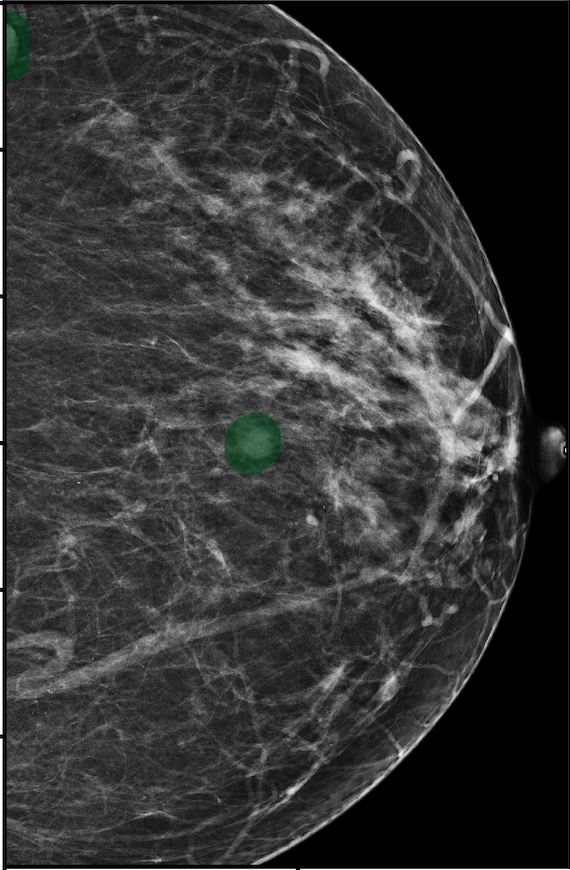

In Figure 7, we visualize saliency maps for four samples selected from the test set. In the first two examples, the saliency maps are highly activated on the annotated lesions, suggesting that our model is able to detect suspicious lesions without pixel-level supervision. Moreover, the attention is highly concentrated on ROI patches that overlap with the annotated lesions. In the third example, the saliency map for benign findings identifies three abnormalities. Although only the top abnormality was escalated for biopsy and hence annotated by radiologists, the radiologist’s report confirms that the two non-biopsied findings have a high probability of benignity and a low probability of malignancy. In the fourth example, we illustrate a case when there is some level of disagreement between our model and the annotation in the dataset. The malignancy saliency map only highlights part of a large malignant lesion with segmental coarse heterogeneous calcifications. This behavior is related to the design of : a fixed pooling threshold cannot be optimal for all sizes of ROI. The impact of is further studied in 3.6. This example also illustrates that while human experts are asked to annotate the entire lesion, CNNs tend to emphasize only the most informative regions. While no benign lesion is present, the benign saliency map still highlights regions similar to that in the malignancy saliency map, but with a lower probability than the malignancy saliency map. In fact, calcifications with this morphology and distribution can also result from benign pathophysiology [42].